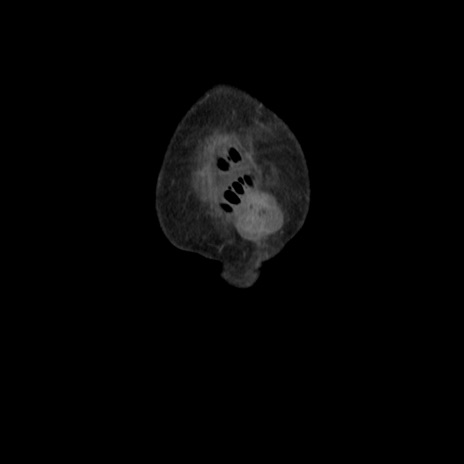

横断像

【症例】80歳代 女性

【主訴】腹部膨満感

【現病歴】他院にて肝硬変にてフォロー中。1週間前から便秘、腹部膨満感、臍部腫瘤あり受診となる。

【既往歴】肝硬変

【身体所見】腹部膨隆あり、皮膚変化なし、疼痛なし。

【データ】WBC 4600、CRP 0.25